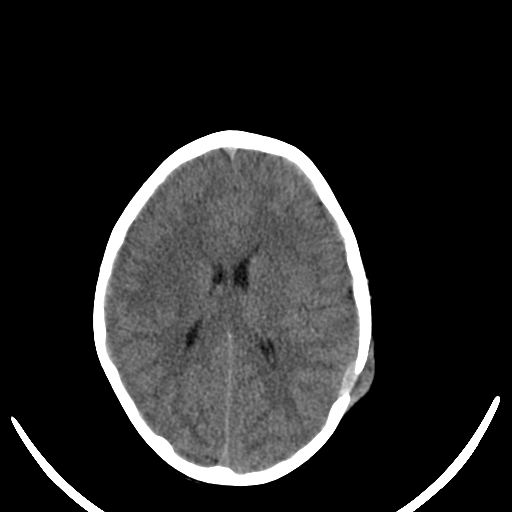

A. � un bambino di 7 anni che giunge in PS per la comparsa di una tumefazione molle in sede parietale sinistra associata a intenso dolore locale ed irritabilit� da alcuni giorni. In anamnesi trauma cranico 15 giorni prima senza sintomi associati. A. � in buone condizioni generali e l'obiettivit�, compresa quella neurologica, � nella norma. Anche gli esami ematici risultano nella norma. Vista la clinica e la storia di trauma cranico, eseguiamo TC cranio che mostra: �in sede extra-assiale parietale sinistra, apprezzabile sottile aspetto tenuemente iperdenso di larghezza 17 mm e spessore 5 mm; in corrispondenza, area tondeggiante di osteolisi di 10 x 10 mm a margini netti, con tumefazione delle parti molli extracraniche�. Per approfondimento diagnostico, eseguiamo RMN cerebrale che evidenzia: �formazione a densit� intermedia di diametro 4 x 2,5 cm in sede parietale sinistra che si localizza su entrambi i versanti del tavolato cranico, a ridosso dell'area di osteolisi.� In considerazione del reperto neuroradiologico, dopo consulenza Oncologica e Neurochirurgica, viene posto sospetto diagnostico di granuloma eosinofilo. Eseguite Rx torace ed eco addome che hanno escluso un possibile coinvolgimento viscerale. A. � stato quindi sottoposto ad intervento di curettage chirurgico che ha dato conferma istologica della diagnosi.